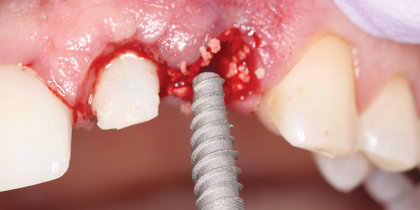

• After extracting tooth #5, a Glidewell HT Implant is immediately placed and a provisional crown delivered, leading to an esthetic, predictable final restoration. thumbnail image

Immediate Provisionalization

After extracting tooth #5, a Glidewell HT Implant is immediately placed and a provisional crown delivered, leading to an esthetic, predictable final restoration.

• A large periapical defect necessitates precise angulation of a Glidewell HT Implant in the extraction site prior to temporization, establishing a stable foundation for the eventual restoration. thumbnail image

A large periapical defect necessitates precise angulation of a Glidewell HT Implant in the extraction site prior to temporization, establishing a stable foundation for the eventual restoration.

• A central incisor is extracted and immediately replaced with a Glidewell HT Implant and provisional crown, facilitating an esthetic final outcome. thumbnail image

A central incisor is extracted and immediately replaced with a Glidewell HT Implant and provisional crown, facilitating an esthetic final outcome.

• A Glidewell HT Implant is immediately placed into an extraction socket to replace a grossly decayed tooth #10, establishing the stability needed for provisionalization and a predictable final restoration. thumbnail image

A Glidewell HT Implant is immediately placed into an extraction socket to replace a grossly decayed tooth #10, establishing the stability needed for provisionalization and a predictable final restoration.

• A Glidewell HT is immediately placed into the extraction socket of a maxillary central incisor. thumbnail image

Extraction with Immediate Placement

A Glidewell HT is immediately placed into the extraction socket of a maxillary central incisor.